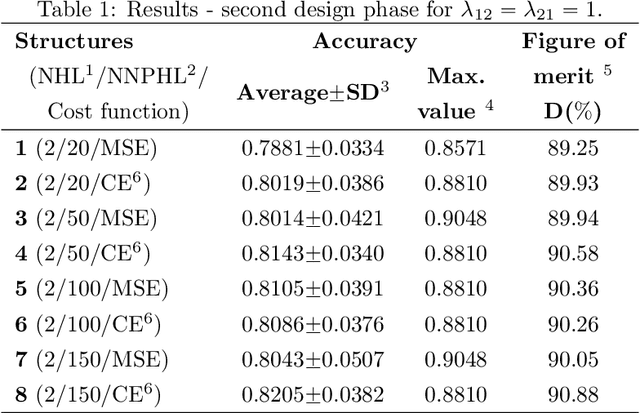

A Pathology-Based Machine Learning Method to Assist in Epithelial Dysplasia Diagnosis

Abstract:The Epithelial Dysplasia (ED) is a tissue alteration commonly present in lesions preceding oral cancer, being its presence one of the most important factors in the progression toward carcinoma. This study proposes a method to design a low computational cost classification system to support the detection of dysplastic epithelia, contributing to reduce the variability of pathologist assessments. We employ a multilayer artificial neural network (MLP-ANN) and defining the regions of the epithelium to be assessed based on the knowledge of the pathologist. The performance of the proposed solution was statistically evaluated. The implemented MLP-ANN presented an average accuracy of 87%, with a variability much inferior to that obtained from three trained evaluators. Moreover, the proposed solution led to results which are very close to those obtained using a convolutional neural network (CNN) implemented by transfer learning, with 100 times less computational complexity. In conclusion, our results show that a simple neural network structure can lead to a performance equivalent to that of much more complex structures, which are routinely used in the literature.